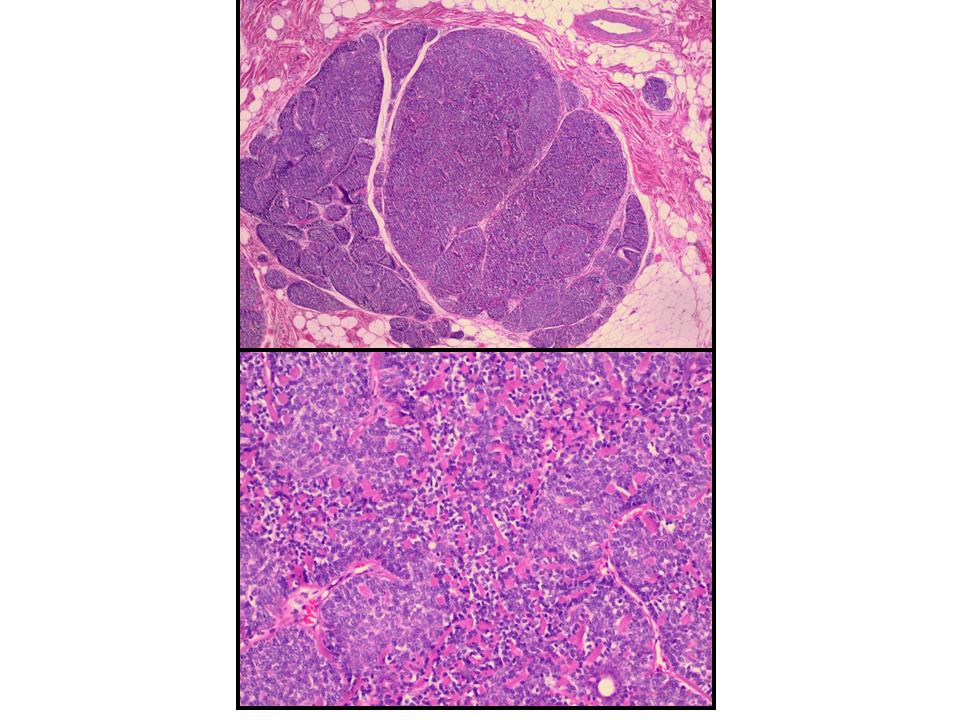

Spir adenocylindroma = الاسطوانوم الغدي العرقي